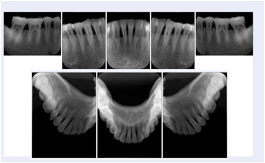

3. A dental provider wishes to capture a series of DICOM IO images for the patient’s dentition. The tooth morphology, teeth are divided into molars, premolars, canines and incisors, and a number of images for each jaw. The anatomic information was captured utilizing the triplet of schema. This standard code sequence is based on ISO 3950-2010, Dentistry - Designation system for teeth and areas of the oral cavity.

Every IO image should have anatomic information either through the primary or modifier sequence.

In most standard cases, images are oriented in structured layouts. These structured displays are useful to be shared between providers for reference purposes.

Table OO.1.1-1 shows structured display standard templates, where Viewset ID is based on the Japanese Society for Oral and Maxillofacial Radiology (JSOMR) classification provided by JIRA (Japan Medical Imaging and Radiological Systems Industries Association, www.jira-net.or.jp). Expected or typical teeth to be imaged location, region and designation codes are based on ISO 3950-2010, Dentistry - Designation system for teeth and areas of the oral cavity. For all the hanging protocols listed in OO.1.1-1, the value to use for Hanging Protocol Creator (0072,0008) is "JSOMR" and the value to use for Hanging Protocol Name (0072,0002) does not include "JSOMR" (e.g., "DL-S001A", not "JSOMR DL-S001A").